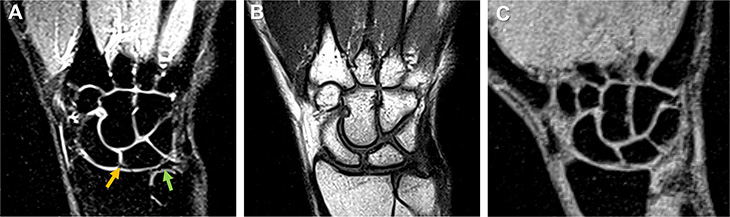

In a proof-of-concept study published in the British Journal of Radiology, UC Davis clinicians and researchers have shown that a new, low-field 0.55T MRI (magnetic resonance imaging) system can create clear videos of moving wrists. This emerging technology could provide important insights to improve diagnoses and better understand wrist anatomy.

In the current study, the team showed the 0.55T machine could produce diagnostic-quality images, either as stills or short, 78 frame-per-second movies. In addition, real-time MRI was incredibly fast. The research team produced high-quality videos in 5 seconds or less. This rapid capture means real-time MRI could improve care without adding significant cost.

“This approach allows us to study the trajectory of structures in an actively moving wrist,” said Szabo. “The dynamic pictures, along with standard, still MRI scans, show us specific wrist anatomy that had never been evaluated to this degree before. This has tremendous relevance to evaluate injuries and conduct further research into how the wrist functions.”